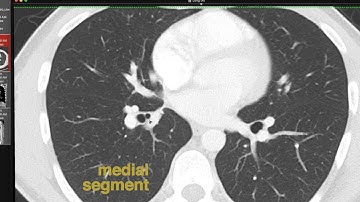

Introduction to CT Chest - Anatomy and Approach